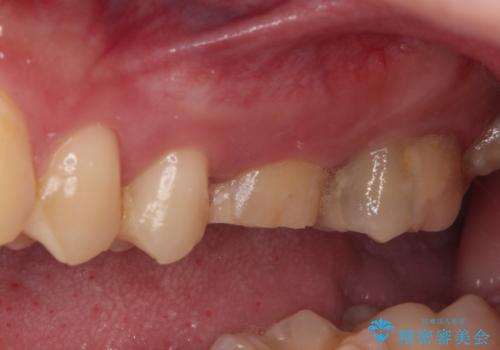

- 近医にて、虫歯が大きいため抜歯が必要と言われたとのことで来院された患者様です。

診査したところ、根尖部の病変は大きいものの、抜歯が必要とは決して思えず、まずは根管治療を行うべきと判断しました。

根管治療後、病変が消退したことを確認し、オールセラミッククラウンにて補綴治療を行うこととしました。